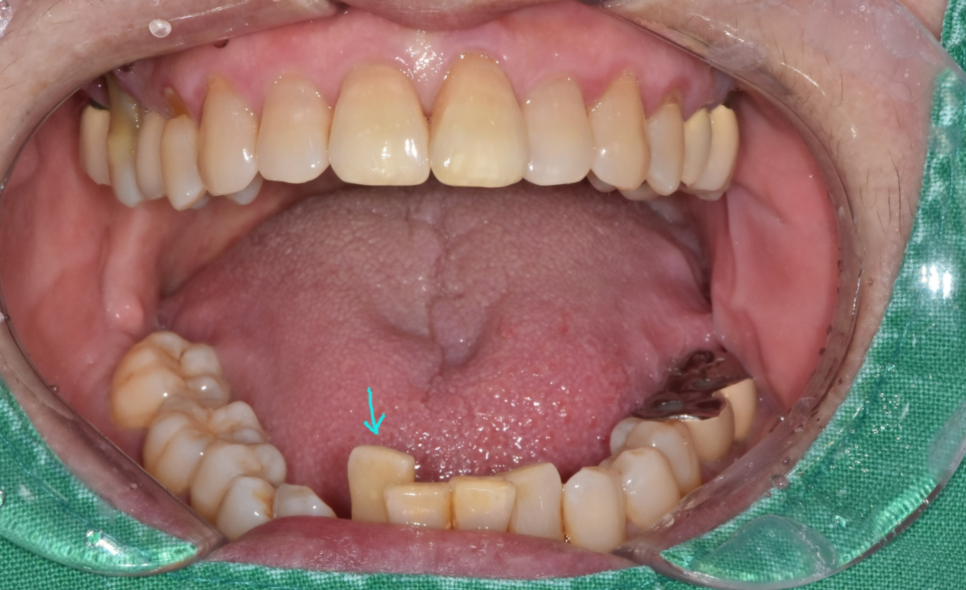

사진을 보시면 아래 앞니 1개가 솟구쳐 올라와있죠?

다른 치아에 비해 키가 유독 큰 모습입니다.

치아가 솟구쳐서 불편해요

240517 붙어있는 치석들